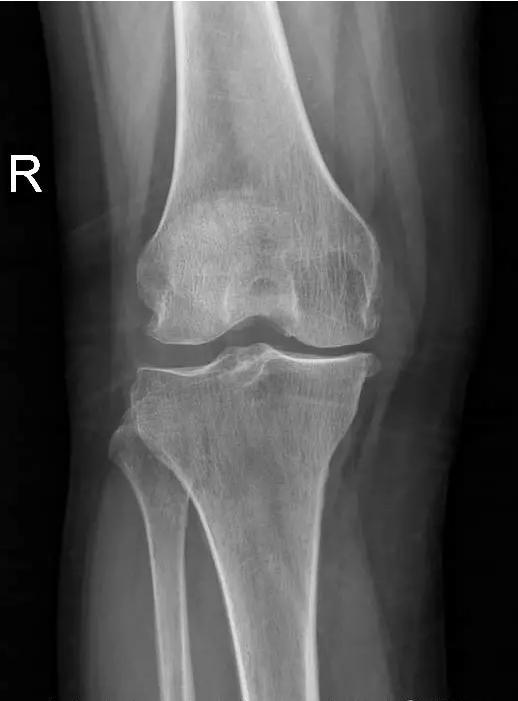

术前片:

对于晚期(重度)骨关节炎,保守治疗无效时,要积极考虑手术治疗。目前效果最佳的手术方式即为关节置换手术,其他手术方式如关节融合手术等效果较关节置换术相差较大,已不在临床广泛使用。关节置换手术的目的是缓解患者疼痛,矫正关节畸形,恢复关节功能,恢复正常生活。对于老年人来说,积极的手术治疗可以有效恢复其日常生活,避免因疼痛及活动障碍导致患者扶拐或坐轮椅,有效减少因缺乏运动导致的心肺功能障碍及精神问题发生。经过几十年的发展,目前关节置换技术已十分成熟,临床上目前采用的微创技术,手术创伤小,术中出血非常少,术后第二天患者即可下地行走,三月之后即可恢复正常生活及功能。至于人工假体使用寿命,目前进口关节多为20-30年,能满足60-70岁患者的需求。需要注意的是,在行关节置换手术之后,患者仍需要进行积极的康复治疗,包括关节活动度及周围肌力的锻炼等,这样才能达到最佳的手术效果。

晚期:骨关节炎表现为膝关节明显疼痛,休息后常无缓解,伴有活动受限,可并发畸形,X 线片可见关节周围有明显的骨赘形成,或可见游离体,关节间隙明显狭窄,甚至消失。